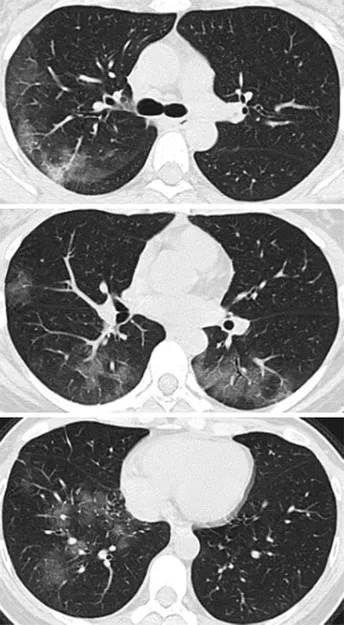

肺部CT扫描(见下图A)

两侧肺上叶肺段呈斑片状毛玻璃样显影。

3天后,再次CT检查发现,

两肺的毛玻璃显影更大了(图片B),

显示治疗效果不好,病情加重。